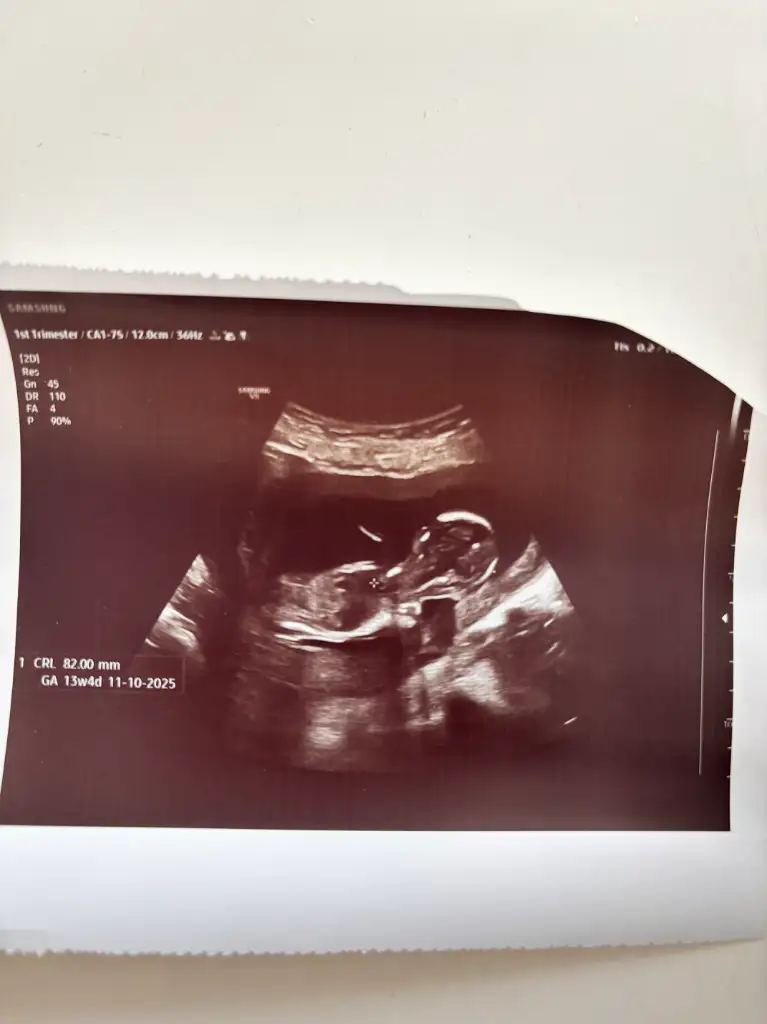

merhabalar banada tahminde bulunur musunuz 8+3 karından ulturason

Erkek bence plasenta yerine göre yorumladım sağlıkla gelsinOglusannesi banada yorum yapar mısınız

şuan 13+4 haftalık